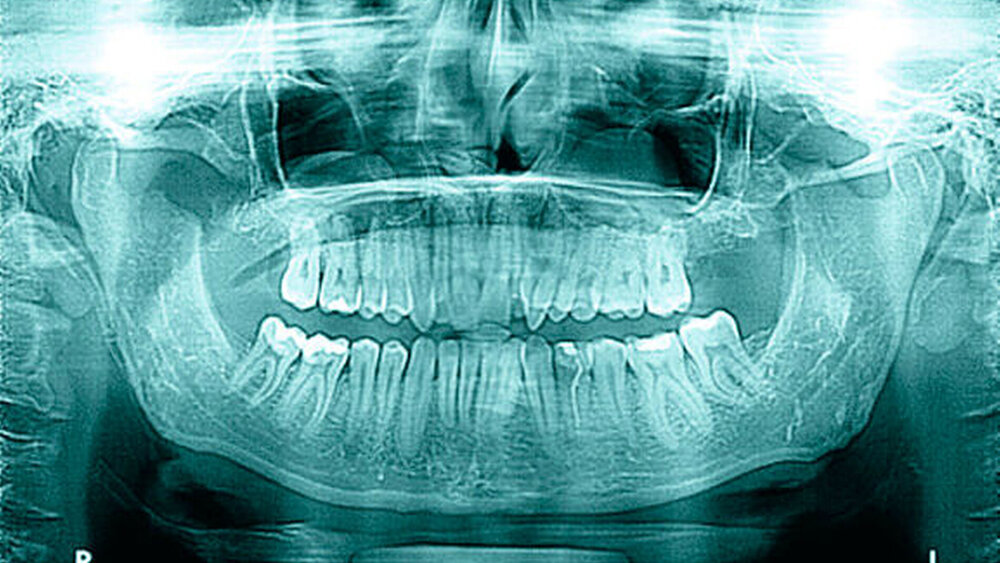

Bei der Befundung des Orthopantomogramms fielen hyperplastische, weit nach cranial extendierende Processus (Proc.) coronoidei beidseits auf (Abbildung 2).